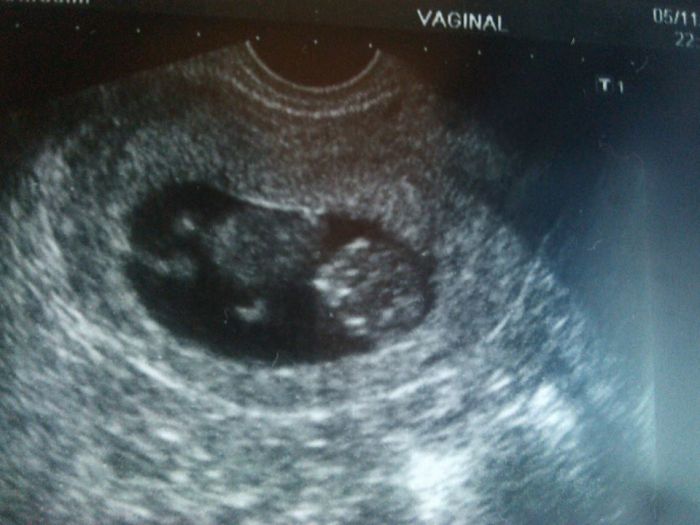

Ahoj holčinky, tak u nás všechno super, máme ručičky, nožičky a srdíčko pořád bije skvěle

a konečně jsem si vzala i fotečku pokusím se ji ofotit. Jsem podle MS a UZT stejně 9+3 a mimi má 26mm, takoví mrně a už tam jde všechno vidět, je to úžasný. Průkazku dostaneme až za 14dní.